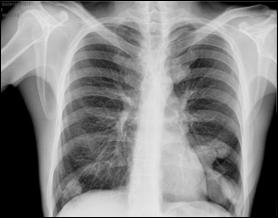

4.5. Radiografia osoasa 4. Radiografia toraco-pulmonara

Figura 44. Metastaza in articulatia coxo-femurala

dreapta Figura 45. Metastaze pulmonare multiple dintr-un carcinom vezical

Figura 4 Radiografie toraco-pulmonara cu metastaze pulmonare multiple

dintr-un carcinom vezical infiltrativ

Figura 47. Radiografie toraco-pulmonara cu metastaze pulmonare multiple dintr-un carcinom vezical infiltrativ.